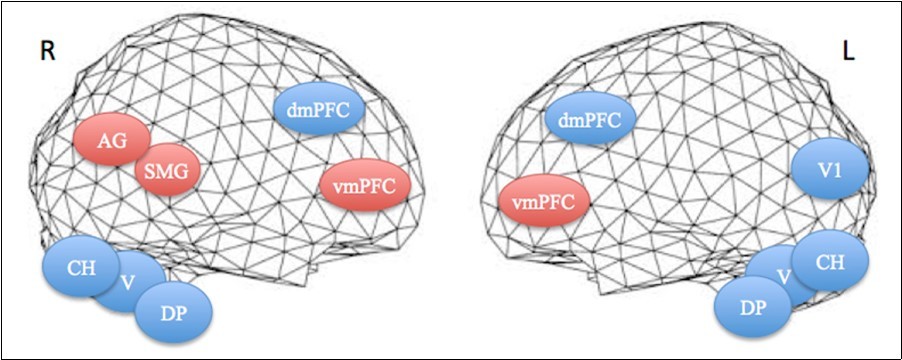

The apnea period was obviously recognizable on the time course of the BOLD signals graphs because of the striking change of the curves from breathing to apnea and after apnea, with very low fluctuations during apnea. Within eloquent brain areas TC curves showed various patterns: (i) high fluctuations mainly in the second half of apnea in the dorsal pons only (Figure 1-1st row), (ii) very low fluctuations with deep depression at the end of apnea in the cerebellum (Figure 1-2nd row) as well as in the supramarginal gyrus (Figure 2, lower row), less marked in occipital areas (figure 1-4th row), and (iii) flat curve in dorsomedial prefrontal (Figure 1-3), ventromedial prefrontal (Figure 2-upper row) and inferior parietal areas (Figure 2-middle row). The eloquent areas disclosed during both experiments are mapped on a brain mesh as nodes of both networks (Figure 3).

Figure 3.Projections of activated areas on a brain mesh showing networks involved in the first apnea (blue labels) and second apnea (red labels). Dorsomedial (dmPFC) and ventromedial prefrontal cortices (vmPFC), dorsal pons (DP), vermis (V) and cerebellar hemispheres (CH) are activated bilaterally, while inferior parietal cortex, including the angular gyrus (AG) and the supramarginal gyrus (SMG), is on the right hemisphere and medial visual cortex (V1) on the left one. R=right. L=left.

We found the dorsal pons (DP), the vermis (V), the cerebellar hemispheres (CH), and the dorsomedial prefrontal (dmPFC) areas to be correlated in the same network, in the first breath hold, and ventromedial prefrontal cortex (vmPFC), angular (AG) and supramarginal gyri (SMG) of the inferior parietal lobe, in the second breath hold. The DP activation might be directly linked to the reticular formation involved in the sympathetic nervous control, likely elicited by urgent breath requirement associated with the first phase of prolonged apnea. The neurochemical control of breath generation, rhythm and hold, is a complex and not yet completely understood field 24. DP nuclei are part of the complex respiratory system including other brainstem nuclei that are sensitive to carbon dioxide levels and acidity, which concentration depends on blood flow and oxygenation. The brainstem interacts with the cortex for breath regulation via the cortico-pontine and reticulo-spinal tracts 24. The functional mapping of the cerebellar hemispheres has shown that lateral lobules VI and Crus I are involved in motor preparation, while upper medial lobules IV and V are involved in motor execution 25. Crus I is connected with the prefrontal cortex and lobules IV, V and VI with the motor cortex 25, 26. These areas (VI and Crus I) are also involved in verbal working memory, a function that could be part of apnea sustaining. In this topological cerebellar organization, the anterior vermis (lobules I-VI) was proven strongly correlated with the motor and somatosensory cortices, and the posterior vermis (lobules VII-IX) with prefrontal (vm- and dmPFC) and inferior parietal (AG and SMG) cortices. These cerebellar activations could be related to the training effect and emotion processes 25. In addition, the cerebrum cortical areas disclosed have interesting implications in active and resting state networks: PFC for decision procedure, awareness, mentalizing capabilities and resting state default mode network as well as for sustaining activity in working memory and monitoring the response selection. Medial occipital activation may implicate the visual stimulation for perceptual awareness and consciousness. The network we observed is likely responsible for sustaining consciousness and decision making ability, including connections with the respiratory regulator system, via a self-representation or out-of-body (OBE) experience 27.